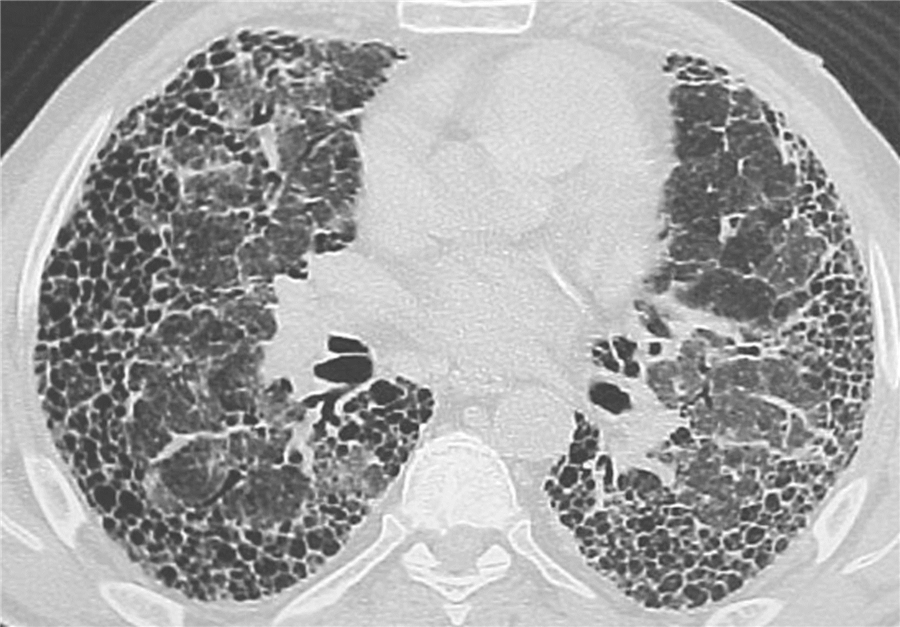

INCREASE kısa adlı randomize-kontrollü faz 3 çalışmasında interstisyel akciğer hastalığı (akciğer sertleşmesi) ve akciğer hipertansiyonu olan hastalarda solunum yoluyla uygulanan treprostinil tedavisinin 16. Haftada 6 dakikalık yürüme testi ile değerlendirilen egzersiz kapasitesini plaseboya göre artırdığı gösterilmişti.

Lancet’ de yayınlanan bu bu post-hoc analizde, inhale treprostinilin genel çalışma popülasyonunda ve çeşitli alt gruplarda FVC üzerindeki etkileri incelendi.

İnhale treprostinil FVC’ de plaseboya göre 8. haftada 28.5 ve 16. haftada 44.4 ml artış sağladı; bunlar FVC’ de yüzde 1.8 artışa tekabül ediyordu.

Alt grup analizlerinde idyopatik interstisyel pnömonisi olanlarda FVC’ nin 8. haftada 46.5 ml ve 16. haftada 108,2 ml, idyopatik fibrozisi olanlarda, 8. haftada 84.5 ml ve 16. haftada 168.5 ml arttığı belirlendi.

İnterstisyel akciğer hastalığı ve ilişkili akciğer hipertansiyonu olan hastalarda, inhale treprostinil, FVC’ de 16 haftada plaseboya kıyasla iyileşmeler sağladı.

Bu fark en çok idyopatik interstisyel pnömonisi, özellikle idyopatik akciğer fibrozisi olan hastalarda belirgindi.

İnhale treprostinil, prospektif, randomize, plasebo kontrollü bir çalışmada idyopatik akciğer fibrozisi için umut verici bir tedavi gibi görünmektedir; bunun daha fazla araştırmayla doğrulanması icap eder.